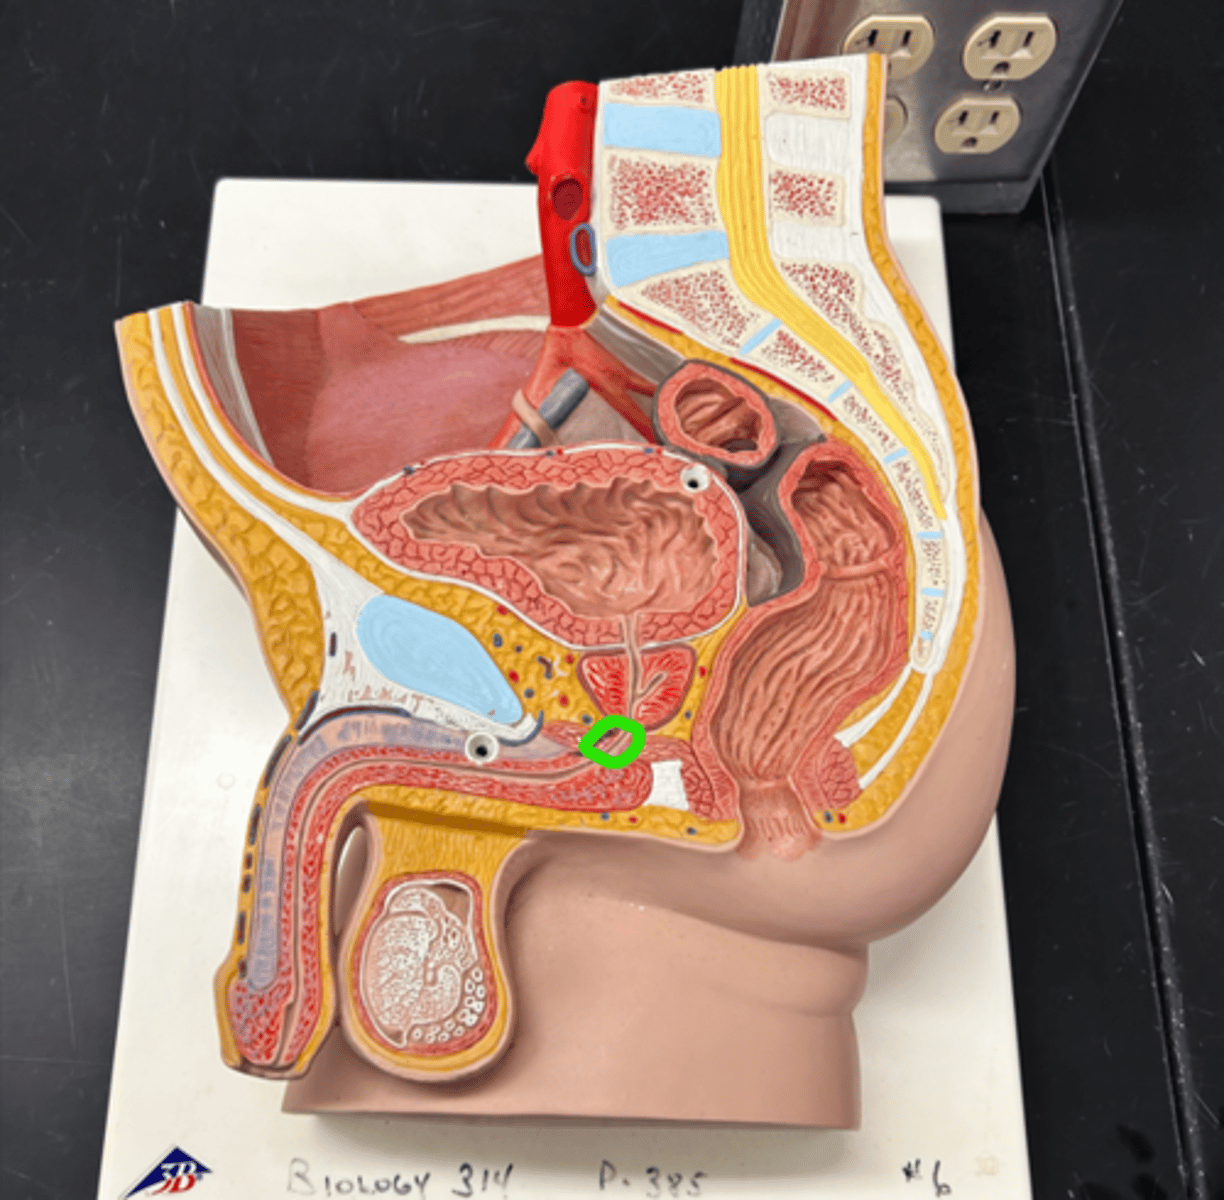

Chapter 30 Anat Phys: Male Reproductive System

Bulbourethral gland

Membranous urethra